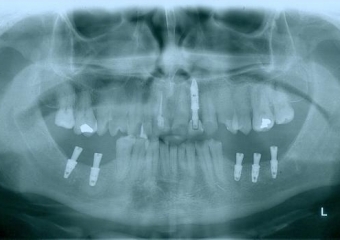

Raio - x Próteses provisórias, em 2015

Próteses Provisórias, em 2015